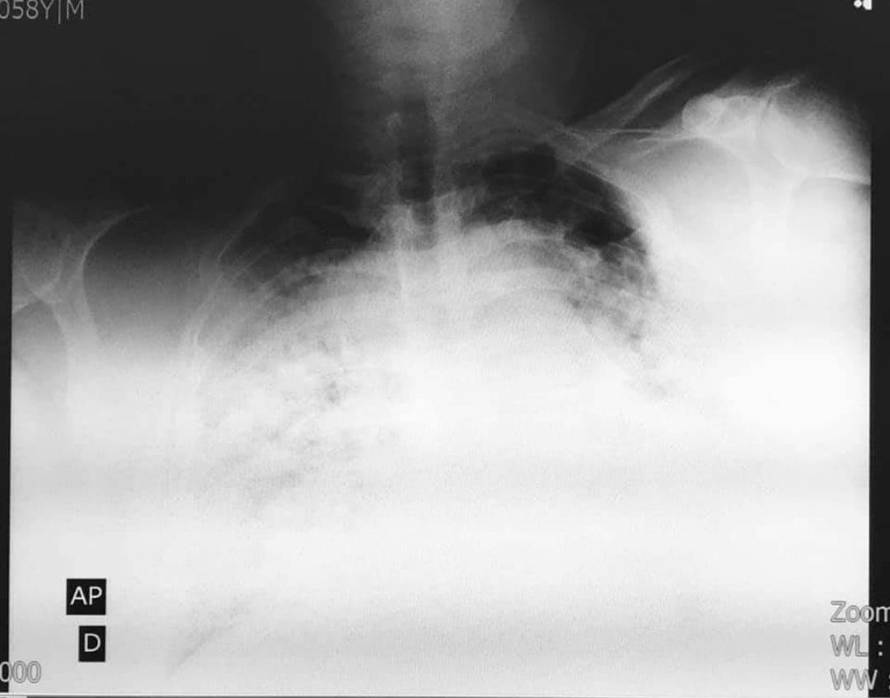

"Pluća su mu gotovo nestala pod virusom, rekao mi je: J..i ga kolega, znam da sam loše..."

Doktor Stevo Vejić bio je na prvoj liniji bitke protiv COVID-a, sve dok nije završio u bolnici normalno je radio, a onda je završio u bolnici zaražen koronom i za deset dana je preminuo